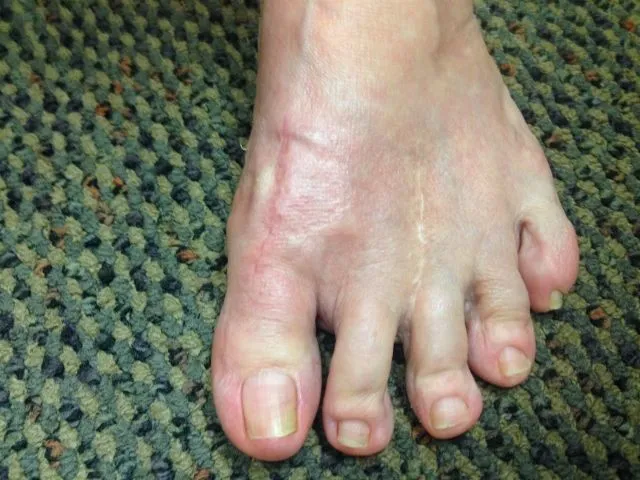

Preop, Immediate postop in OR anf 6 months status post bunionectomy with first metatarsal osteotomy

Pre and Immediate Post Op Pics of Bunionectomy with First Metatarsal Osteotomy